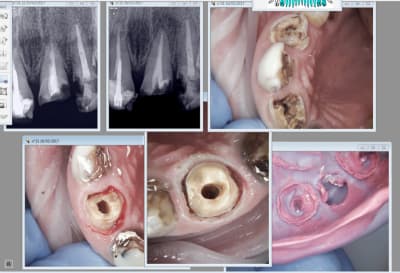

Tiens suite de mon Ic à 4 pattes empreinte prise le 9 03 et pose aujourd'hui. Aspect de la gencive encourageant après le coup de laser.

Capture d écran 2017 03 20 13.14 - Eugenol

J'ai d'ailleurs récidivé pour l'empreinte de la couronne. -)

Capture d écran 2017 03 20 13.19 - Eugenol

Cette 14 pas trop mal.

Capture d écran 2017 03 20 13.26 - Eugenol